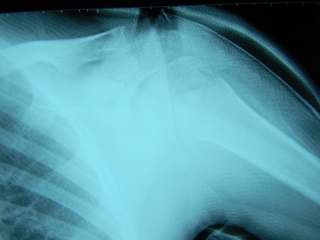

H25.2.23 14歳男子

柔道試合中投げられた際左肩から落下し、捻り受傷。

左肩関節の前方脱臼と、解剖頚の骨折です。

末梢牽引からゼロポジションにもっていきながら脱臼の整復をし、

キャストライトにて胸郭を開き、外転60度、内分回し30度にて固定しました。